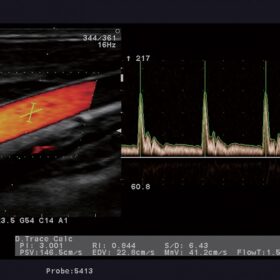

Ultrasound Aloka Prosound Alpha 6 – Image Gallery and Videos

- High blood flow definition: eFLOW

- Automated IMT Measurement

- eTRACKING (Echo Tracking)

Aloka UST-5413 Vascular Linear